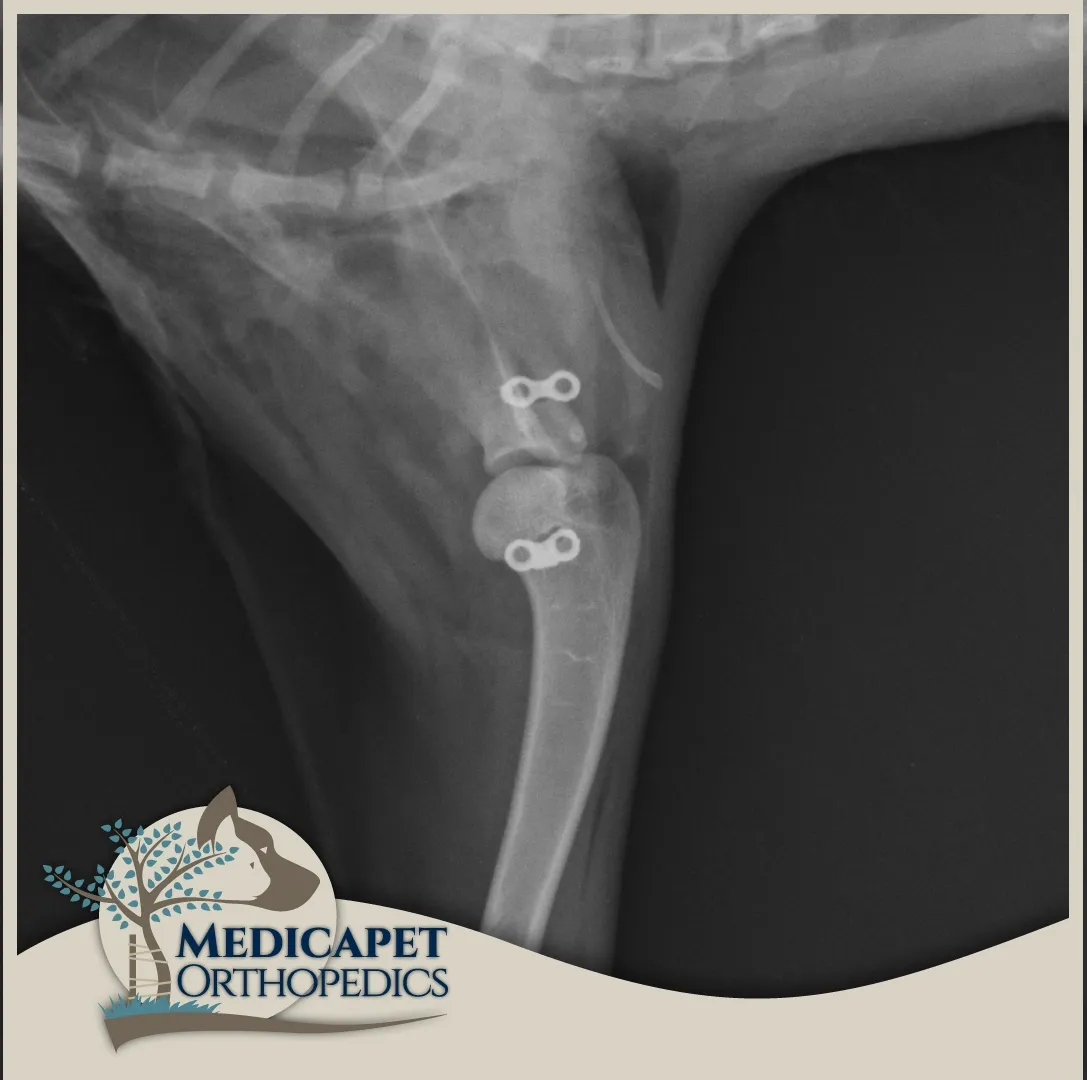

Tedavi

Tedavide eklem kapsülünün fazla yırtılmadığı ve bağların kopmadığı olgularda ameliyatsız kapalı redüksiyon yoluna gidiyoruz. Fakat omuz etrafındaki yumuşak dokuların ağır hasarlarında kapalı olarak yerine oturtulabilse bile omuz tekrar çıkacağından cerrahi tedavi uyguluyoruz. Kapalı redüksiyon ve açık ameliyat sonrası 2 haftalık bir süreçte atel uygulaması genellikle elzemdir. Cerrahi tedavi amacıyla Toggle Pin ve sentetik bağlardan faydalanıyoruz.